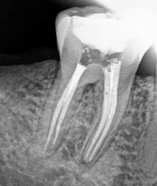

Es un procedimiento que

tiene como finalidad evitar la perdida del diente.

Para ello, se extrae la pulpa dental, se desinfecta y posteriormente se rellena y sella con material inerte y biocompatible.

¿Qué es una endodoncia?